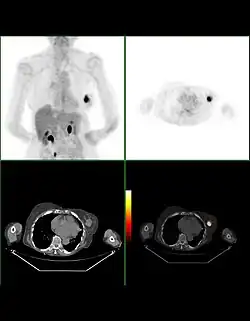

Die Befundung des PET- oder PET/CT-Bildes erfolgt durch Betrachtung der rekonstruierten Schnittbilder (axial, koronar oder sagittal). Bei PET/CT-Geräten ist die Darstellung von PET und CT verknüpft, so dass automatisch die Position des korrelierenden PET-Bildes gezeigt wird, wenn der Bildkursor im CT-Bild verschoben wird.

Für eine Übersichtsdarstellung wird ein sogenanntes MIP-Bild (Maximum Intensity Projection) herangezogen. In dieser Darstellung ist das gesamte Untersuchungsobjekt abgebildet und man erlangt einen schnellen Überblick über Regionen erhöhter Aufnahme. Zur nochmals besseren Visualisierung kann man das MIP um sich selbst rotieren lassen, um das Untersuchungsobjekt von allen Seiten zu zeigen.

Bei der Beurteilung einer Anreicherung muss zwischen physiologischem und pathologischem Uptake unterschieden werden. Ein Uptake kann ganz unterschiedliche Ursachen haben: Ein Tumor kann ebenso zu einer FDG-Anreicherung führen wie das Heilen einer Wunde, ein Entzündungsvorgang, eine einfache Muskelanspannung oder ein frierender Patient.[16]